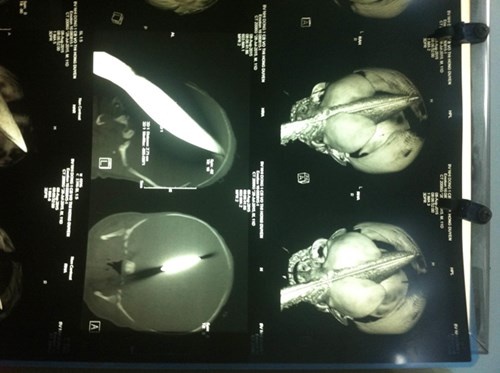

| Hình chụp CT con dao đâm sâu vào não bé. Ảnh: Bệnh viện cung cấp. |

Sau 3h phẫu thuật khẩn cấp các bác sĩ đã lấy con dao dài 28 cm, ngang 2,7 cm, ra khỏi đầu bé. Chiều cùng ngày công an đã bắt nghi phạm. Do nghi phạm gặp vấn đề về sức khỏe nên lực lượng chức năng cho vào Khoa Nội (Bệnh viện Đa khoa Vĩnh Long) theo dõi, dưới sự giám sát của lực lượng công an.